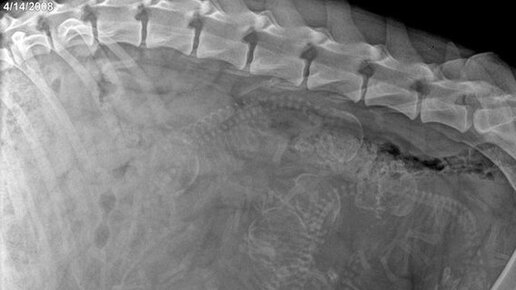

Фото: Рентген беременной собаки

Может я ненормальная, но мне это кажется очень милым. Просто посмотрите, как это прекрасно. Удивительно, как они там все умещаются внутри и не калечат друг друга. Рентген позволяет узнать количество щенков и размеры таза собаки, чтобы роды прошли удачно...

Чем все-таки закончится наше уже привычное самозаточение? Демографический взрыв или алкогольный апокалипсис? Надеемся на лучшее, поэтому сегодня говорим о беременности. Собак, разумеется. Эти 2 месяца ожидания превращают веселого питомца в милое неповоротливое существо. Давайте посмотрим, как это бывает: На снимке этой глубоко беременной далматинки я насчитала 10 щенков, кто увидит больше? Кстати, самое большое количество щенков в одном помете было 29, по другим данным 24 (а в России — 19 щенков у среднеазиатской овчарки Эрики из Новгорода в 2016 году)...